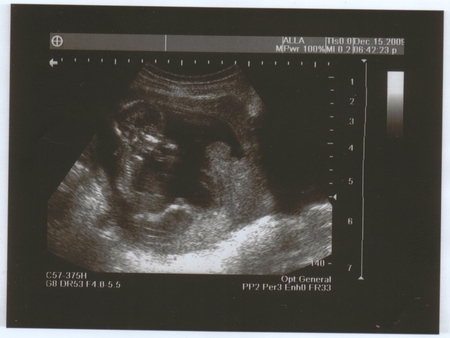

Даже в сегодняшнем гороскопе на ББ написано, что у меня целый день будет блаженное настроение до самого вечера! Ладно, ближе к теме)))) Кароче, пришла я на УЗИ, живот намазали, и тетя-врач в монитор смотрит и говорит, что малыш большой, здоровый, всё на месте, на неделю больше своего срока, то есть, срок по месячным у меня 14 недель и 4 дня, а по УЗИ 15 недель и 4 дня!))) о как!!! Богатырь или богатырша!!!! Переднее предлежание плаценты.. или чего-то там... КТР - 95 мм.Сказала, что у меня все отлично, ни тонуса, ни чего-то ещё.. все в порядке))) Потом повернула монитор и я увидела своего малыша. Она мне ласково начала рассказывать, где ножки, ручки.. да я и сама все видела!!!! Это на фотках плохо видно, а в живую, когда он шевелится - отлично. Я видела всё!!! Он мне и махал и палец сосал!))) Действительно, было состояние блаженства. Я только охала и ахала, просто удивлялась.. не ужели.. этот живой малыш у меня в животе?!)))) Вот и малыш и вопрос, что на 3-й фотографии??? Мы с мужем не поняли))) кто знает, напишите, пожалуйста!)))

здорово! на третьей фотке похоже головка сверху и там разметки такие это размер головки меряли)) я тоже делала узи, на 17 недели, мне тоже ставили на неделю больше срока, и сказали что похоже на девочку)) фото получилось очень отчетливое, смотрю и любуюсь)) так приятно...